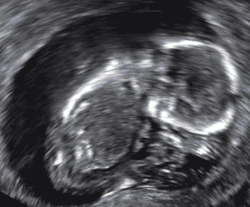

Diagnosis

In the case of blood loss, pain, or both, transvaginal ultrasound is performed. If a viable intrauterine pregnancy is not found with ultrasound, blood tests (serial βHCG tests) can be performed to rule out ectopic pregnancy, which is a life-threatening situation.[107][108]

A miscarriage may be confirmed by an obstetric ultrasound and by the examination of the passed tissue. When looking for microscopic pathologic symptoms, one looks for the products of conception. Microscopically, these include villi, trophoblast, fetal parts, and background gestational changes in the endometrium. When chromosomal abnormalities are found in more than one miscarriage, genetic testing of both parents may be done.[109]